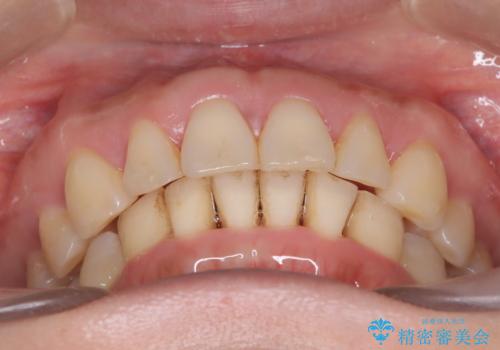

- 前歯が出ていることを主訴に来院されました。

インビザラインにて臼歯部の遠心移動及びIPRを行なっています。

叢生量が多いケースでしたが、綺麗な歯並びとなり患者様にも満足していただきました。

非抜歯矯正のため口元の変化はありません。